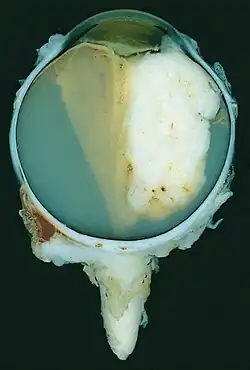

| A pathology specimen of a retinoblastoma tumor from an enucleated eye of a 3-year-old female | |

Gross and microscopic appearances of retinoblastoma are identical in both hereditary and sporadic types. Macroscopically, viable tumor cells are found near blood vessels, while zones of necrosis are found in relatively avascular areas. Microscopically, both undifferentiated and differentiated elements may be present. Undifferentiated elements appear as collections of small, round cells with hyperchromatic nuclei; differentiated elements include Flexner-Wintersteiner rosettes, Homer Wright rosettes,[31] and fleurettes from photoreceptor differentiation.[32]

-

Drawing of a large retinoblastoma -